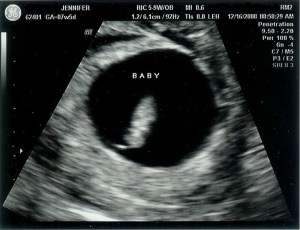

We called the doctor and told them that we were pregnant and that we had an ultrasound scheduled for December 16 and could we still keep the appointment to check the progress of the pregnancy. They said yes! Another transvaginal (ug!) ultrasound. On December 16 I was 7 weeks and 5 days along when we got to see our precious baby for the first time. We were so relieved to see the little heart beating. It was such a different feeling from seeing the empty sac during our first pregnancy.